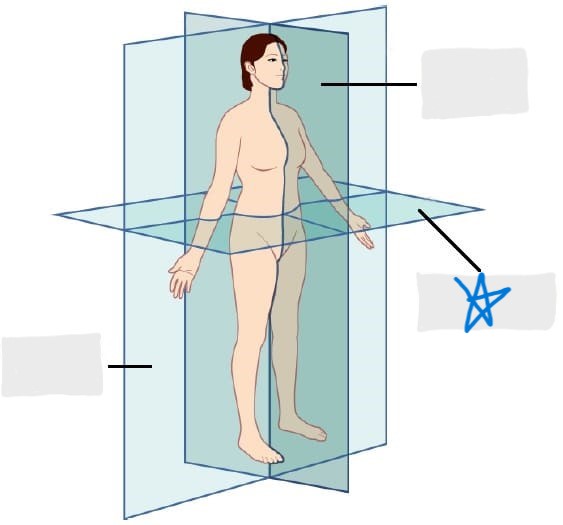

sagittal plane

frontal/coronal plane

transverse plane